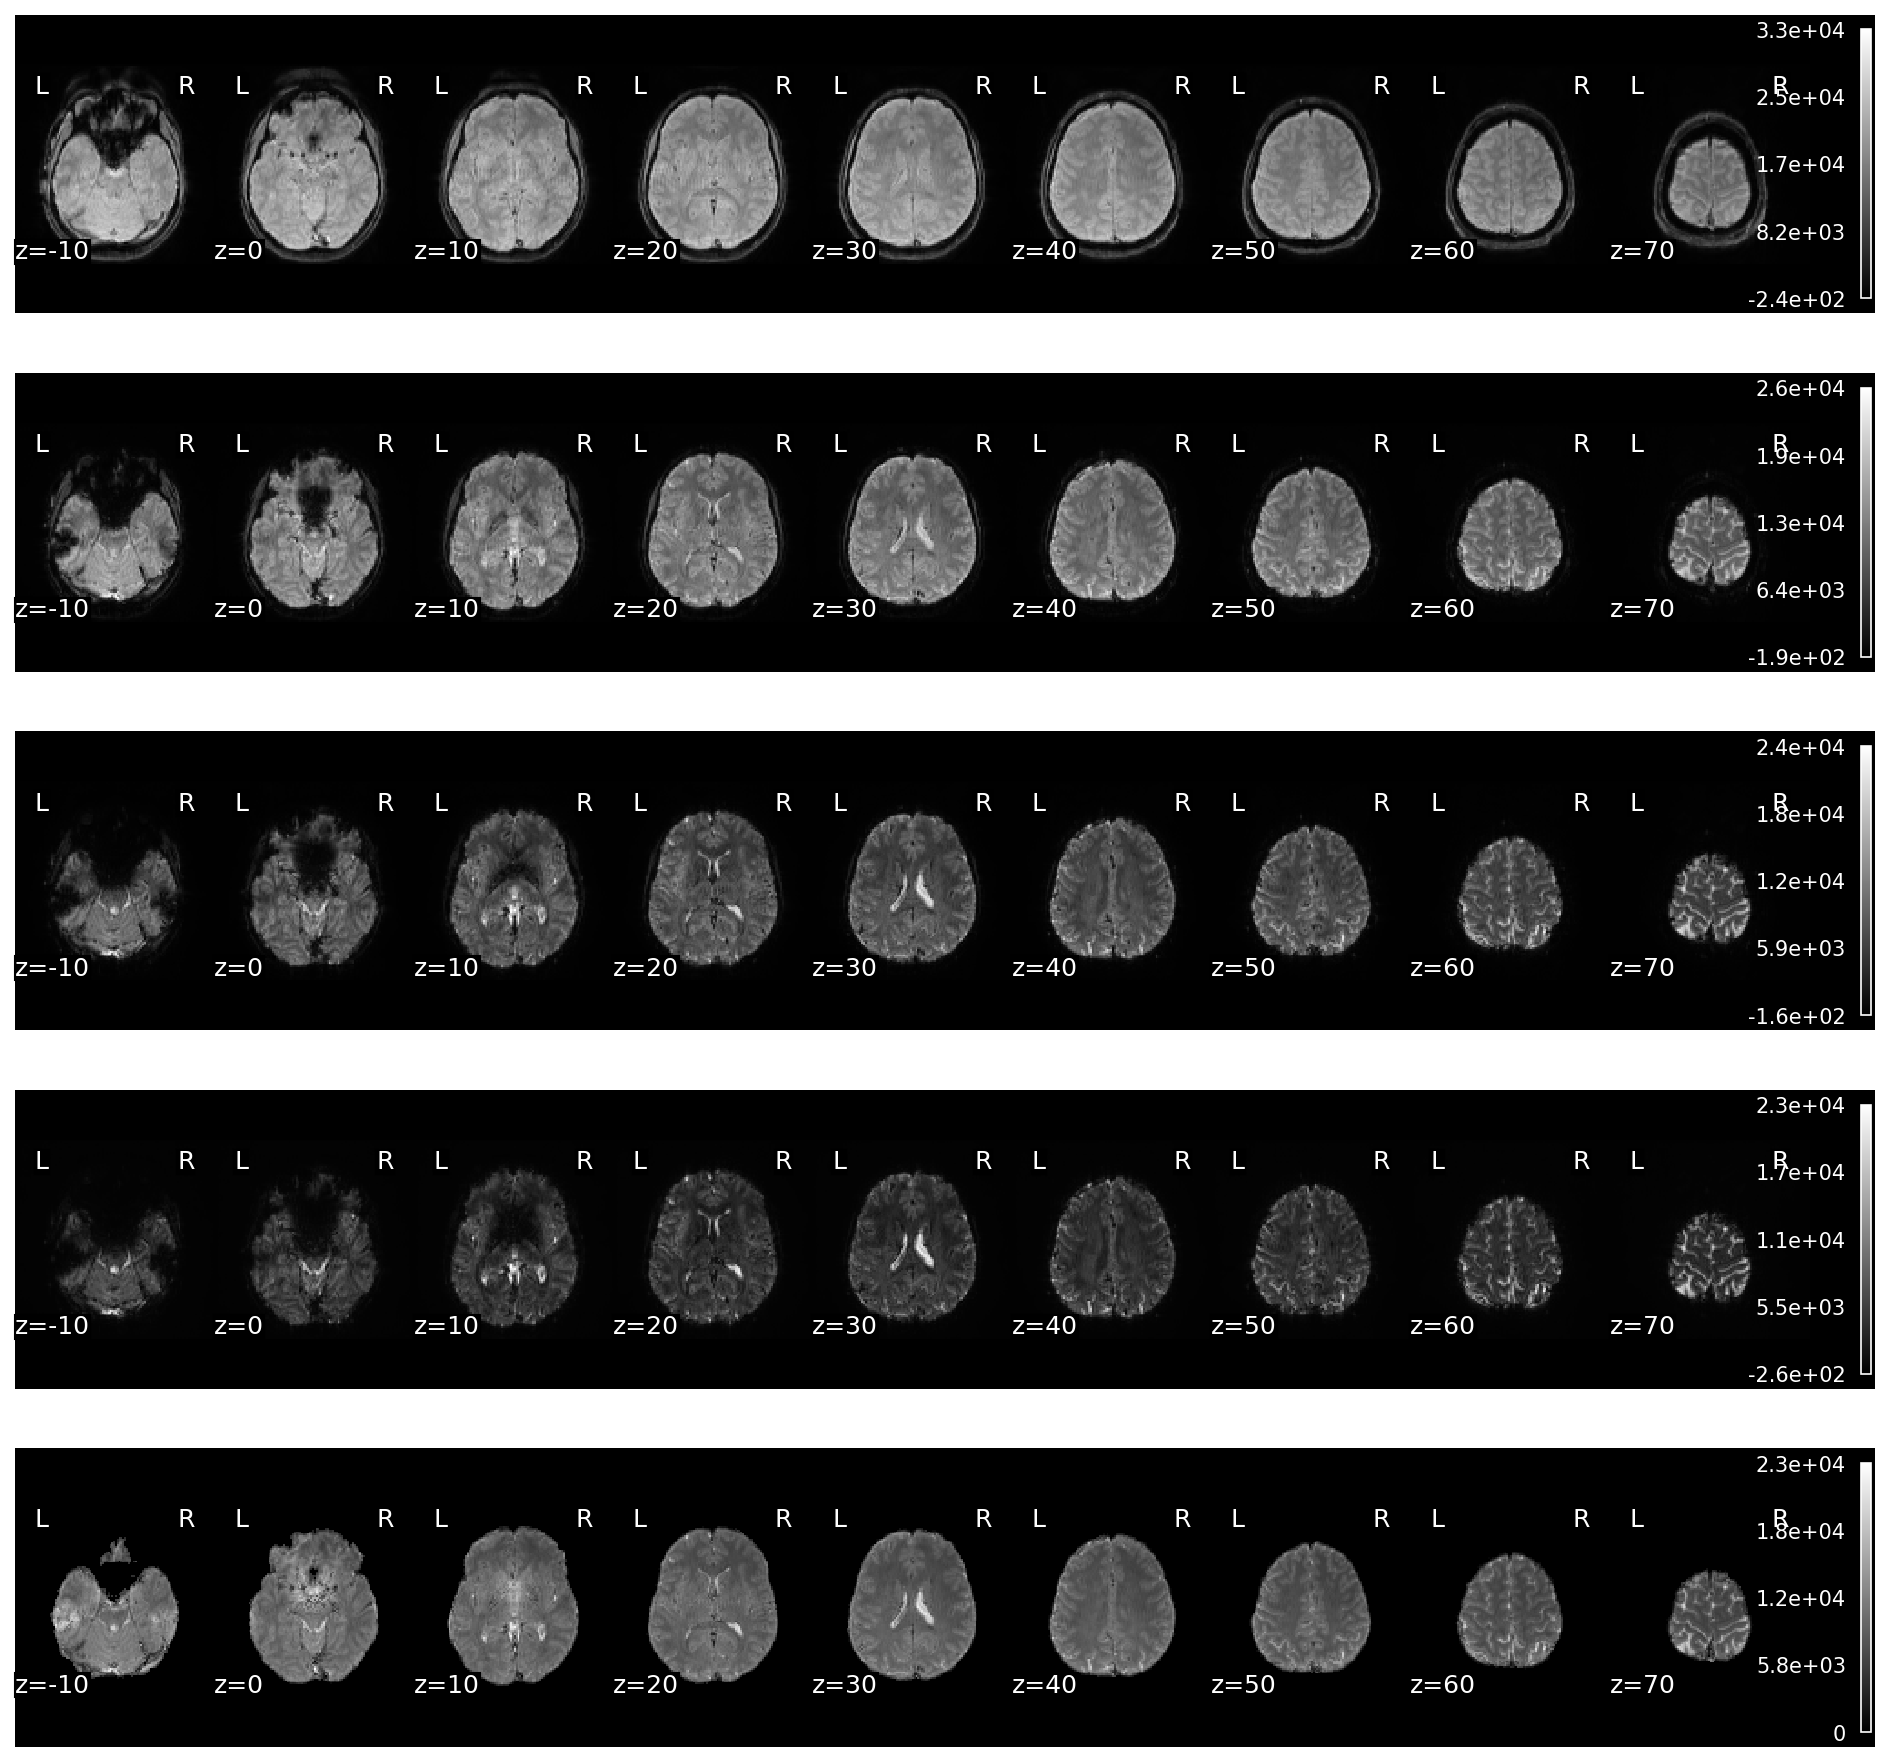

glue_figure("figure_mean_echos_and_optcom", fig, display=False)

../_images/ee5dcb3e5d965e8a549a5a61bca70fd043cef5a743ae837eab10229f010bc92f.png

Fig. 31 Mean images of the echo-wise data and the optimally combined data.#